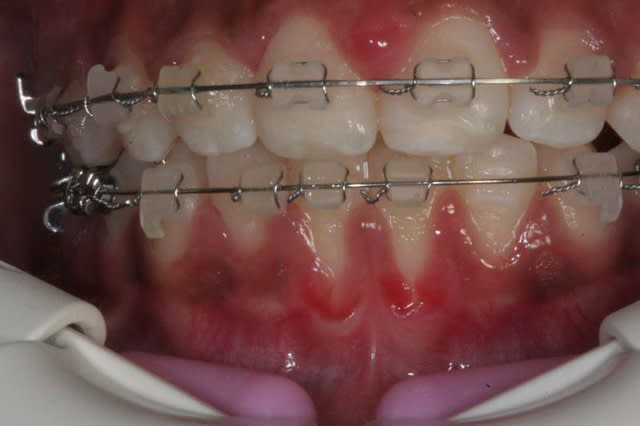

06/03/2010 à 19h50

Suite

Le reformage d’arcade est en cours

La béance commence à se réduire, car la langue se repositionne et l’interposition linguale Ant. diminue, ce qui laisse les forces biologiques de l’orbiculaire agir

@ suivre Bjc.

Sur la photo précedente, on est en 16*x16* à mémoire de forme et en friction Damon

j’ai Tjs. un Pb. de rotation sur les Inc. Inf.

aussi j’ai changé les Bk . céramique Inf. pour des Bk. titane, qui ont meilleure glisse, j’ai mis un ressort de Root (D gainer chez Damon), et Bk. 35/34/33/43/44/45 en position inter-active (Roncone pour éviter la rotation distale de 33/43 qui se produirait avec un système passif Damon)

+ un Arc 20*x20* à mémoire de forme pour redresser les axes canins

+ un segmenté 32/42 avec un arc 16*x16* et les Bk. en position inter-active (Roncone) pour déroter les Inc. Inf.